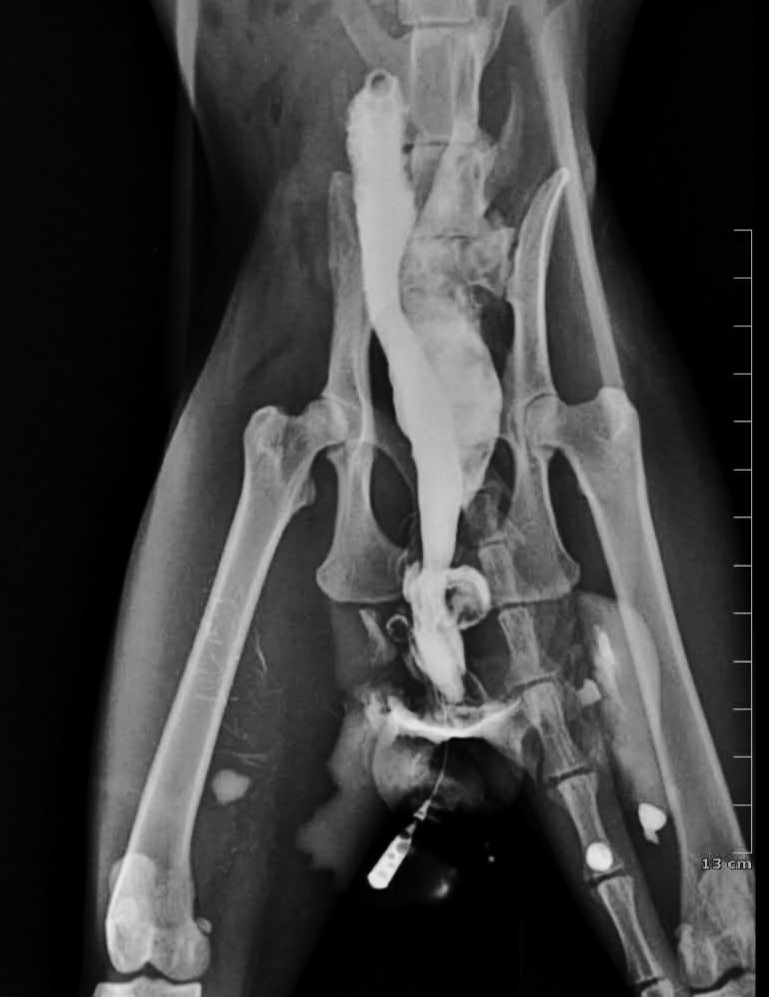

A 6 years old cat presented to us with recurrent episodes of of UTI infection.

Radiographs

In the light of the given radiographs, What is the most probable diagnosis ?

Here's Why :

• Chronic urinary signs

• Recurrent UTI with severe bacteriuria

• Perineal moisture

• Anal irritation

• Contrast study showing leakage of contrast into the rectum with abnormal communication between the urethra and the rectum